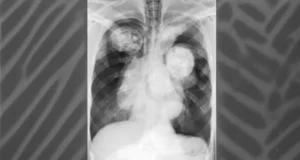

Dr Pallavi Purwar offers cutting-edge surgical treatment for Aspergilloma / Fungal Lung Disease, offering hope to patients grappling with this complex condition.